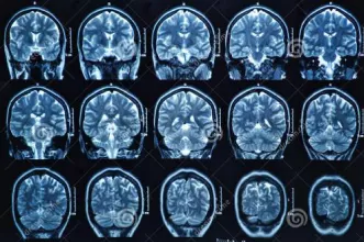

MRI也就是磁共振成像,屬于斷層成像的一種,它是利用磁共振現象從人體中獲得電磁信號,并重建出人體信息。通過檢查可獲得橫斷面、矢狀面、冠狀面的影像,空間分辨率高,是神經系統、脊柱脊椎部分檢測的第一選擇。

無論是DR還是CT,由于對部分軟組織的分辨率不足,所以軟組織疾病的排查便成了它們的短板,而磁共振的長處恰恰就是清晰顯示軟組織疾病,對于膀胱、直腸、子宮及關節肌肉的檢查優于CT。MRI適用于神經系統病變、心血管系統、胸部病變、全身軟組織病變等。